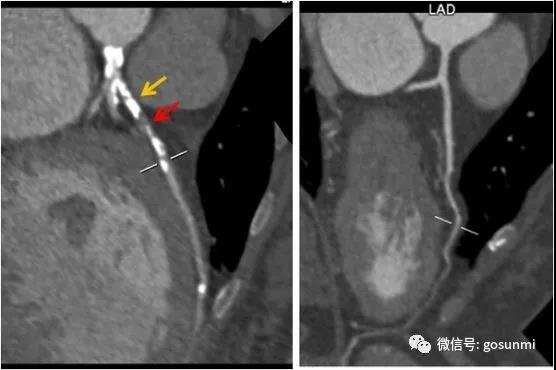

通過(guò)冠脈CTA三維重建,可以再現(xiàn)冠狀動(dòng)脈的形態(tài)、走行,從中了解冠脈的通暢情況。當(dāng)出現(xiàn)冠狀動(dòng)脈粥樣硬化時(shí)(如下圖所示),我們可以看到冠脈的管壁變厚了,并且出現(xiàn)了鈣化斑塊及部分軟斑塊、管腔不均勻的變窄現(xiàn)象。一般當(dāng)出現(xiàn)重度狹窄(狹窄程度>75%)時(shí)便需要進(jìn)行積極的臨床干預(yù)。(左圖為重度狹窄的前降支,黃箭為鈣化,紅箭為軟斑塊、重度狹窄部位,而右圖為正常的左冠前降支)。